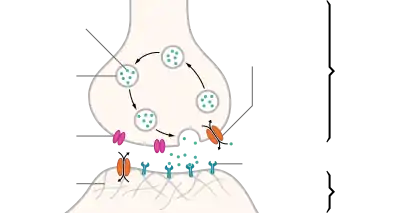

Neurotransmitter transporters are a class of membrane transport proteins that span the cellular membranes of neurons. Their primary function is to carry neurotransmitters across these membranes and to direct their further transport to specific intracellular locations. There are more than twenty types of neurotransmitter transporters.[1]

Vesicular transporters move neurotransmitters into synaptic vesicles, regulating the concentrations of substances within them.[2] Vesicular transporters rely on a proton gradient created by the hydrolysis of adenosine triphosphate (ATP) in order to carry out their work: v-ATPase hydrolyzes ATP, causing protons to be pumped into the synaptic vesicles and creating a proton gradient. Then the efflux of protons from the vesicle provides the energy to bring the neurotransmitter into the vesicle.[3]

Neurotransmitter transporters frequently use electrochemical gradients that exist across cell membranes to carry out their work. For example, some transporters use energy obtained by the cotransport, or symport, of Na+ in order to move glutamate across membranes. Such neurotransporter cotransport systems are highly diverse, as recent development indicates that uptake systems are generally selective and associate with a specific neurotransmitter.[4]

Normally, transporters in the synaptic membrane serve to remove neurotransmitters from the synaptic cleft and prevent their action or bring it to an end. However, on occasion transporters can work in reverse, transporting neurotransmitters into the synapse, allowing these neurotransmitters to bind to their receptors and exert their effect. This "nonvesicular release" of neurotransmitters is used by some cells, such as amacrine cells in the retina, as a normal form of neurotransmitter release.[5]